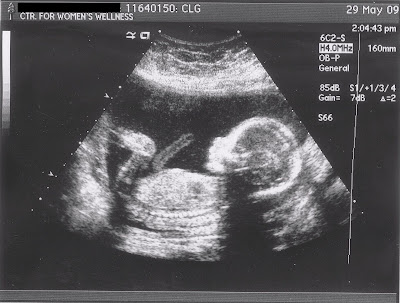

Nothing new to report! I'm starting to feel her move a lot more now, but GG and hubby still can't feel it from the outside. I'm trying to get out sometime soon to get the paper pictures from the ultrasound scanned onto some kind of digital media so I can put them on here. GG and I tried to do it on Tuesday but the power was out at the store we went to. So other than being tired and having a minor "crowded" feeling in my chest, I'm feeling all right!!